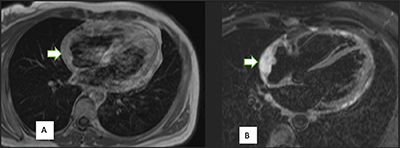

本文讨论了原发性心脏肿瘤的罕见性,尤其是血管肉瘤,占原发性心脏肿瘤的 10%。文章强调了非特异性症状给早期诊断带来的挑战。文章强调了切面成像,尤其是计算机断层扫描(CT)在紧急情况下的重要性。教学要点:尽管原发性心脏肿瘤非常罕见,但放射科医生仍应保持警惕,尤其是出现心包积液时。

This article discusses the rarity of primary cardiac tumors, particularly angiosarcomas, accounting for 10% of primary cardiac neoplasms. The article highlights the challenge of early diagnosis due to nonspecific symptoms. The importance of sectional imaging, particularly computed tomography (CT) scans, in emergent situations is emphasized. Teaching point: Despite the rarity of primary cardiac tumors, radiologists should remain alert, especially when pericardial effusion is present.